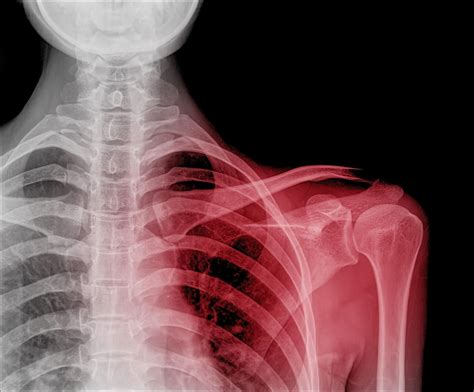

Subluxation in pediatric patients can occur in various joints, but it is most commonly observed in the shoulder, elbow, and knee. Unlike dislocations, which involve a complete separation of the joint surfaces, subluxations are partial dislocations that can be reduced more easily. However, they still require prompt and appropriate management to prevent long-term complications.

Shoulder Trauma, repetitive stress, congenital conditions Pain, swelling, limited range of motion, instability